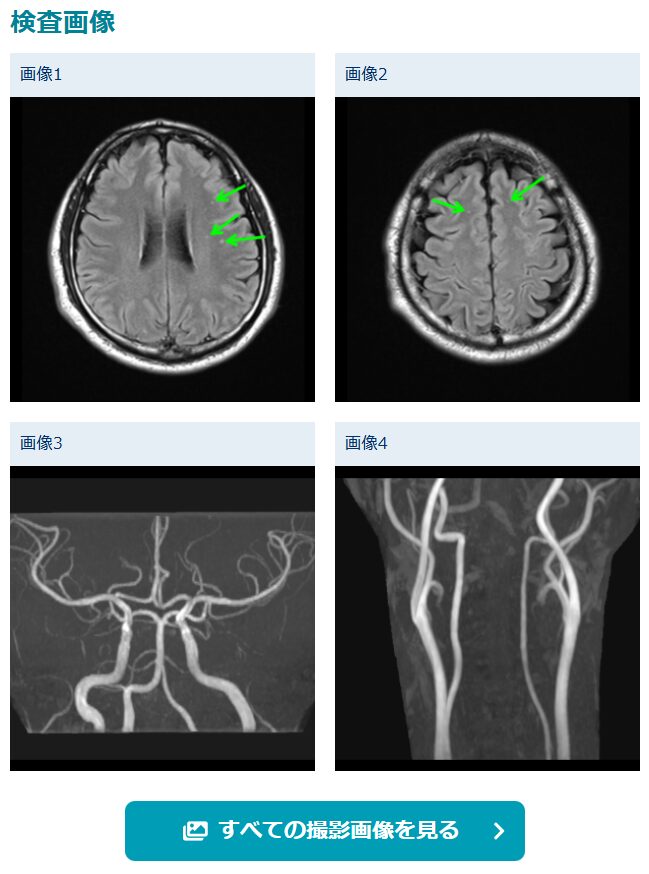

生活習慣病の影響なのか、軽度の脳白質病変が認められたようです😭

この[すべての撮影画像を見る]ボタンから、脳の断面図を連続的に確認できます。マウスのスクロールホイールでぐりぐりと変化します。

MRI初見は以下のとおりです。先ほどあったように、DSWMHがグレード1です。

MRA初見は以下のとおりです。異常なしとなりました。